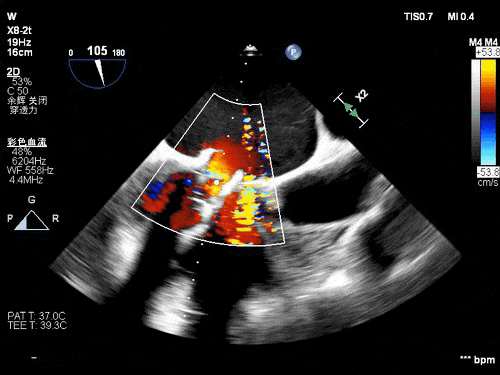

术后TEE图像

瓣膜释放后超声观察无瓣周漏,峰值流速0.76m/s,峰值压差5mmHg,平均压差2mmHg,流出道峰值流速1.28m/s,峰值压差7mmHg。